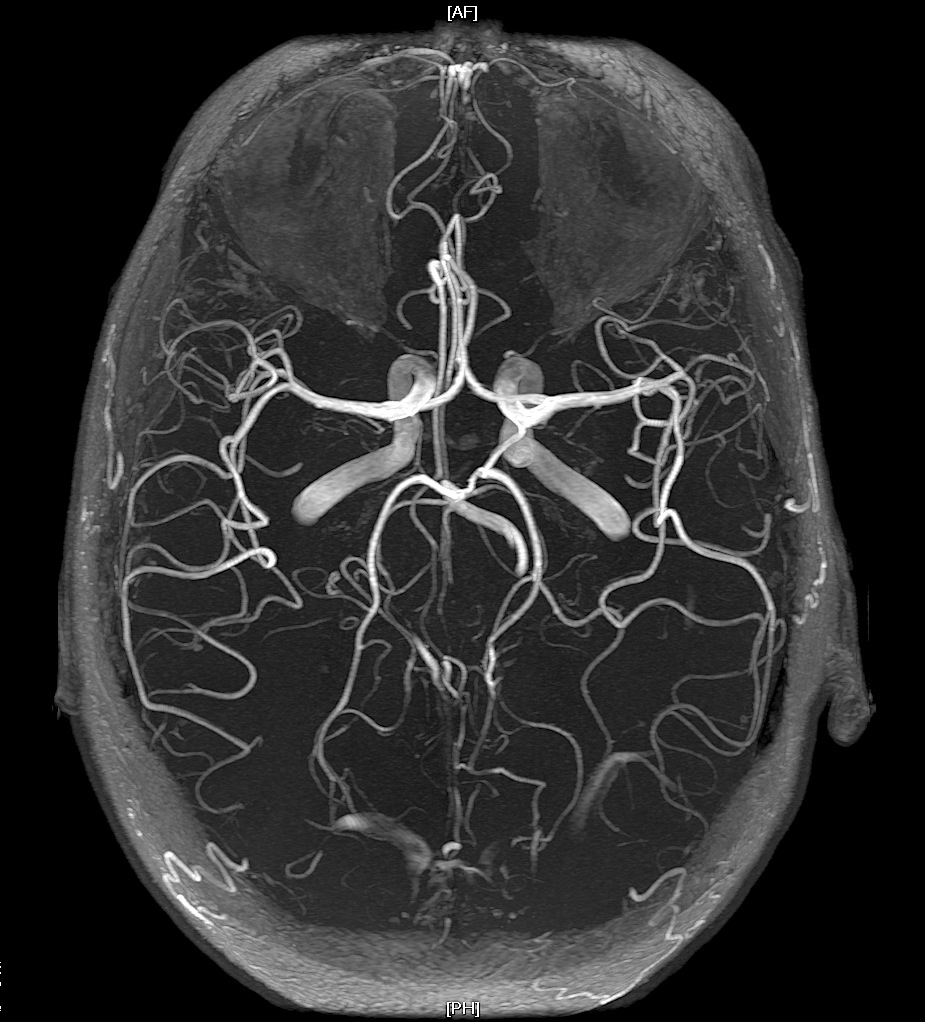

CT Angiography

- CTA uses sophisticated computer analysis to provide detailed, 3D images of the blood vessels. It is a quick and useful test particularly for diagnosis large vessel occlusion and selecting patients for thrombectomy. CTA can provide useful information on vascular anatomy. It has better spatial recognition than MRA but is not as good as DSA. It requires an injection of radiocontrast usually Iodine containing which can cause renal effects and allergies.

- CTA also requires a significant dose of radiation. CTA is almost as accurate as DSA at picking up extracranial stenosis and is more accurate the more severe the stenosis. CTA is useful for diagnosing dissection. CTA is very good at detecting intracranial stenosis. CTA is superior to MRA TOF and in most cases is superior to MRA. Often times however the choice of test also depends upon what is available and most convenient. It is avoided when there are issues with contrast allergies and renal disease and the eGFR must be known.